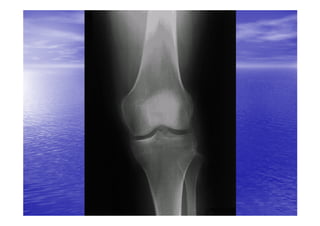

RADIO-

RADIO-ANATOMIE

• Le genou peut être exploré par les incidences

radiologiques suivantes:

– La radiographie standard de genou face/profil

– Arthrographie grâce à l'injection à l'intérieur de la

cavité articulaire du genou d'un produit de contraste

radio-opaque , on peut étudier l’épaisseur des

cartilages articulaires , les ligaments croisés , surtout

les ménisques.

– Arthrographie et scanner.

– IRM.est un excellent moyen d'étudier les ménisques ,

les ligaments , les cavités articulaires et les éléments

squelettiques.